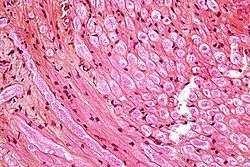

![]() Micrograph showing nerve fibers in a nerve root. HPS stain. | |